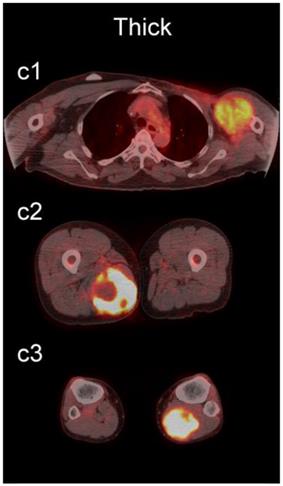

The readers scored the SP of the STSs and BFs on the 4-point avidity scale (Fig. 1). Reader agreement was substantial (κ = 0. 61) and varied among the different SPs, being highest for the thin SP (κ = 0.70) and lowest for the thick SP (κ = 0.46, Table 4). Examples of SPs with 100% reader agreement are shown in Fig. 3.

Figure 3

Examples of lesions with 100% observer agreement on assessment of SP. a Thin SP a1 A 77-year-old woman with a seroma (arrow) 17 days following excisional nodal biopsy (SUVmax = 1.7). a2 A 66-year-old woman with a seroma (arrow) 3 months following excisional nodal biopsy (SUVmax = 2.0). a3 A 21-year-old man with a seroma (arrow) 10 days following excisional nodal biopsy and hydrocele repair (SUVmax = 3.9). b Moderate SP: b1 A 46-year-old man with undifferentiated sarcoma (SUVmax = 19.4). b2 A 38-year-old man with a fungal abscess (SUVmax = 11.6). b3 A 78-year-old woman with recurrent myxoid pleomorphic undifferentiated sarcoma (SUVmax = 5.9). c Thick SP: c1 A 67-year-old man with metastatic undifferentiated sarcoma (SUVmax = 6.3). c2 A 65-year-old man with pleomorphic undifferentiated sarcoma (SUVmax = 30.3). c3 A 45-year-old man with synovial sarcoma (SUVmax = 10.9). d Solid SP: d1 A54-year-old woman with rhabdomyosarcoma (SUVmax = 15.7). d2 A 43-year-old man with pleomorphic undifferentiated sarcoma (SUVmax = 2.7). d3 A 48-year-old woman with myxoid liposarcoma (SUVmax = 2.9).

The SP of STSs was more likely to be assessed as thick or solid by all readers (p<0.0001). Modeling the diagnostic efficacy of a system that classified lesions with a thick or solid SP as an STS yielded an inter-reader averaged sensitivity and specificity of 69% and 98%, respectively.

We also examined the contribution SP to the differentiation of STSs from BFs. SP has not been as extensively investigated as SUV [36-42], and may provide additional information about the biological behavior of soft-tissue lesions on 18F-FDG PET [37]. SP can be assessed qualitatively or quantitatively. Qualitative assessments of heterogeneity, degree of peripheral nodularity, and apparent peripheral thickness of lesions have been used in the past to differentiate benign from malignant lung [38] and peripheral nerve sheath [39] tumors, and to distinguish between high-grade and low-grade STSs [36]. Quantitative algorithms for objective characterization of SP have been used to estimate prognosis in patients with STSs [37, 40, 41] and to assess treatment response in patients with head and neck cancers [42]. Widespread adoption of these quantitative methods has likely been hampered by practical concerns such as time constraints in busy clinical practices. We chose to focus on a qualitative assessment of SP to provide a more readily applied clinical method using an intuitive 4-point scale (Fig. 1) for subjective evaluation of SP (Fig. 3).